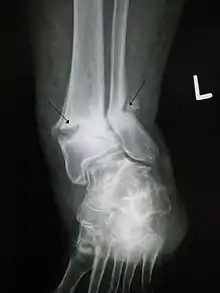

- Trimalleolar fracture – involving the lateral malleolus, medial malleolus, and the distal posterior aspect of the tibia

- Bimalleolar fracture – involving the lateral malleolus and the medial malleolus

- Pott's fracture